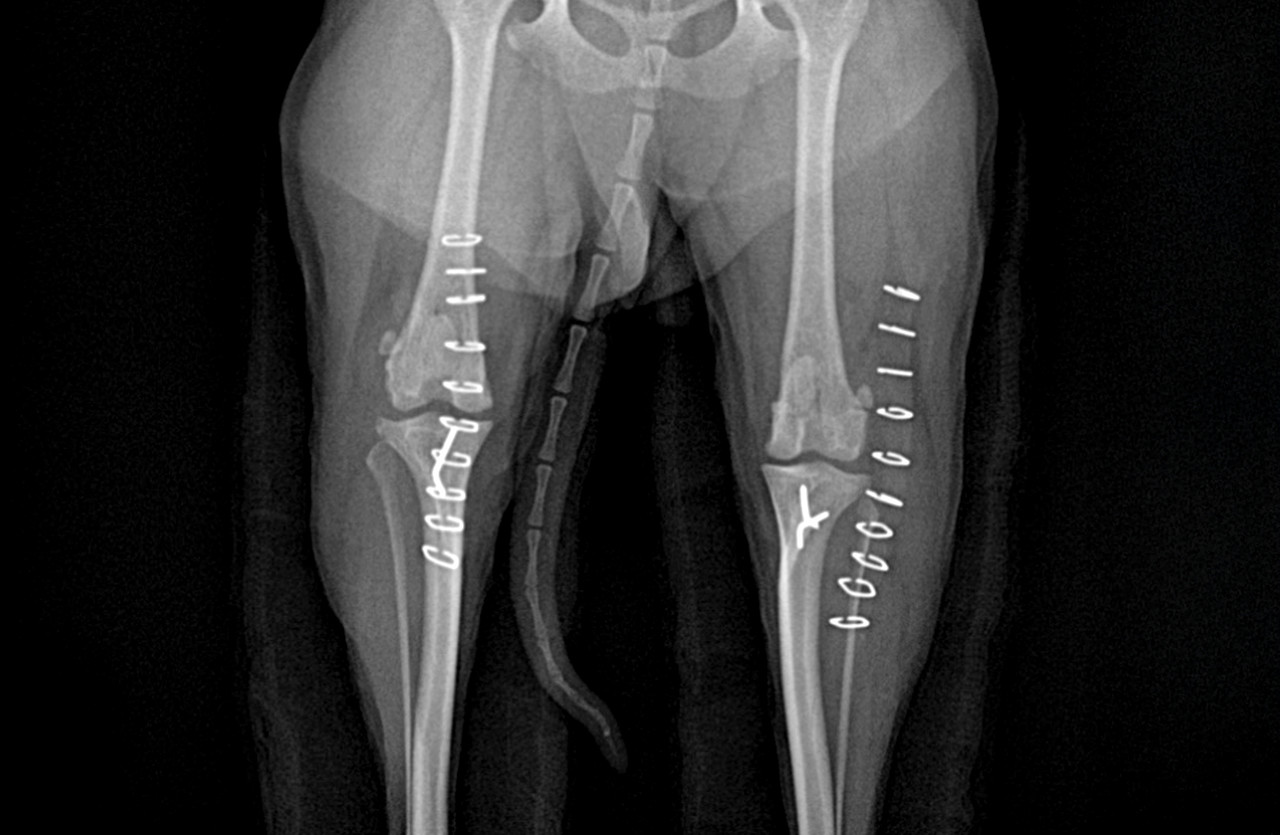

정형외과 다양한 수술

휴 동물의료센터에서는 보행이상을 발생시키는 골관절 질환과 관련하여 다양한 정형외과 수술을 정확하고 안전하게 시행하고 있습니다.

외부 충격으로 인해 다양한 골절이 발생할 수 있습니다.

휴 동물의료센터에서는 환자의 상태를 정확하게 진단하여 치료 효과를 높이고 휴유증을 최소하는 맞춤형 치료가 시행됩니다.

플레이트 스크류 장비

SYNTHES / biortho / Doiff / Able

골절된 뼈를 고정하기 위해 사용하는 의료용 자재입니다.

체내에 부착되고 체형, 뼈 구조, 골절 형태 등에 따라 맞춤형으로 각각 다른 종류를 사용하게 됩니다.

휴 동물의료센터에서는 안전하고 효과적인 치료를 위해 프리미엄급 플레이트 스크류를 사용하고 있습니다.